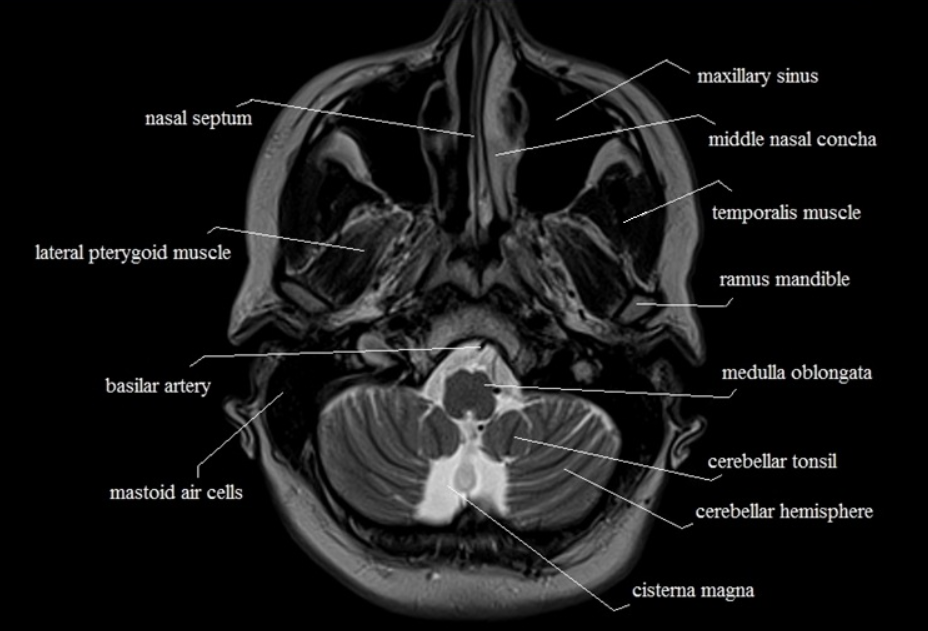

올라가다 보면 뒤쪽으로 소뇌가 나오고 연수(medulla)가 나온다. 연수는 소뇌와 분리되어 있음을 알 수 있다. 아래에서부터 올라가다가 소뇌가 나온다면 소뇌의 아랫부분정도의 level에서 medulla가 나온다.

교뇌가 처음 나오는 컷이다. 교뇌는 소뇌과 연결되는 것처럼 보인다. 소뇌와 연결되는 부분처럼 나오는 level에서는 연수가 나온다.